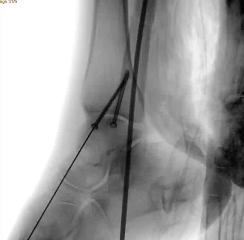

针对王女士的踝关节骨折情况,由副主任医师陈涛主刀,足踝外科团队为其实施了关节镜辅助下机器人导航微创闭合复位内固定术

整个手术通过微创方式开展,全程操作注重精准与安全:

• 通过 5 毫米小切口将关节镜探入关节腔内,清理腔内淤血与致炎因子,清晰观察骨折块移位及关节软骨损伤情况;

• 在关节镜直视下,使用微创器械将骨折块复位至解剖位置,恢复关节面平整;

• 依托机器人导航系统,规划螺钉置入通道,避开关节面与重要组织;

• 最后通过另外两个 5 毫米的小孔置入空心螺钉,完成骨折端的稳定固定。

整个手术仅通过三个 5 毫米的小切口完成,最大程度降低了手术创伤。